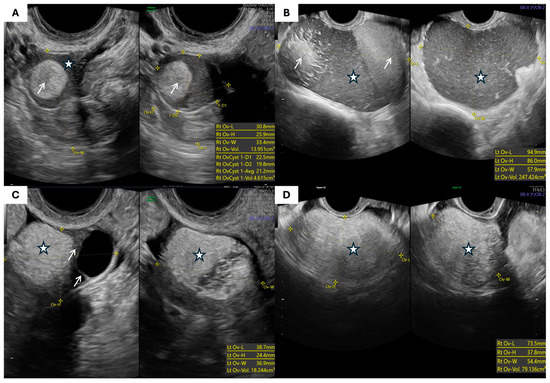

- Morphological Parameters: The morphological assessment included the largest tumor diameter, volume (calculated using the prolate ellipsoid formula: length × height × width × 0.523), laterality, capsule thickness, and internal echogenicity (categorized as anechoic, homogeneous low-level “ground-glass”, hyperechoic, or mixed/heterogeneous). The presence of septa, papillary projections, solid components, acoustic shadowing, free fluid in the pouch of Douglas, and signs of tumor fixation were also recorded.

| The largest tumor dimension (mm), mean ± SD | 78.2 ± 3.3 | 81.9 ± 4.3 | 0.6 |

| Tumor volume (cm3), mean ± SD | 247.9 ± 65.2 | 254.3 ± 75.3 | 0.7 |

| Tumor capsule thickness (mm), mean ± SD | 2.87 ± 1.1 | 2.9 ± 1.1 | 0.9 |

| Septal thickness (mm), mean ± SD | 2.6 ± 0.7 | 2.7 ± 1.4 | 0.7 |

| Free fluid in the pouch of Douglas, n (%) | 1 (2.1%) | 2 (4.3%) | 0.500 |

| Tumor fixation **, n (%) | 7 (14.9%) | 3 (6.4%) | 0.200 |

| Tumor localization, n (%) | 0.042 * | ||

| Unilateral | 39 (83.0%) | 45 (95.7%) | |

| Bilateral | 8 (17.0%) | 2 (4.3%) |

| Morphological Type (IOTA Terminology) | Endometriomas (n = 55) | % | Teratomas (n = 49) | % | p-Value |

| Unilocular cyst with ground-glass echogenicity | 25 | 45.5% | 0 | 0% | <0.001 * |

| Unilocular solid cyst with hyperechoic content | 1 | 1.8% | 10 | 20.4% | |

| Multilocular cyst | 8 | 14.5% | 5 | 10.2% | |

| Multilocular solid cyst | 9 | 16.4% | 25 | 51.0% | |

| Cyst with papillary projections (unilocular or bilocular) | 1 | 1.8% | 1 | 2.0% | |

| Solid tumor | 3 | 5.5% | 4 | 8.2% | |

| Other/not otherwise specified | 8 | 14.5% | 4 | 8.2% |